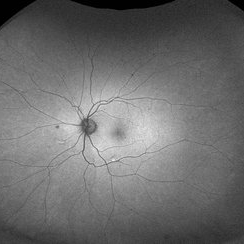

Autofluorescence of a 50 year-old patient with spontaneous giant RPE rip.

Photographer: Mr Veda Vyas

Imaging device: Heidelberg HRA

Condition/keywords: RPE-rip